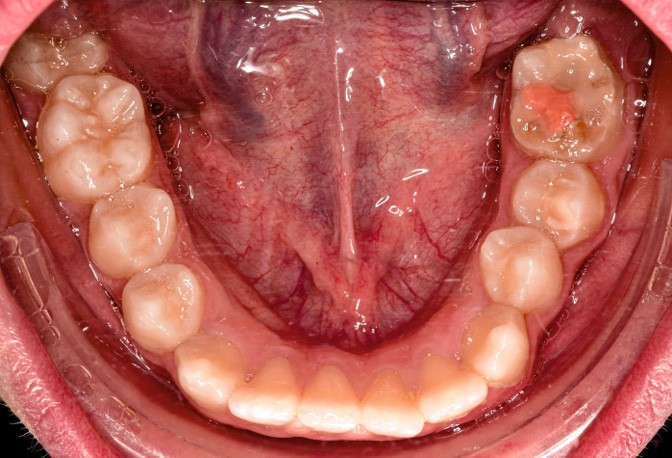

L’examen clinique montre une MIH sévère sur 16, 26, 36 et 46, et modérée sur 11 et 21.

Sur le plan alvéolo-dentaire (fig. 1b) :

- Classe II subdivision gauche avec déviation du point inter-incisif mandibulaire à gauche ;

- occlusion inversée entre 22 et 32 ;

- dysharmonie dento-arcade (DDA) sévère ;

- 13 en position haute retenue.

Sur le plan squelettique : Classe II, schéma hypodivergent (fig. 1c). Sur le plan fonctionnel : aucune dysfonction ni parafonction.